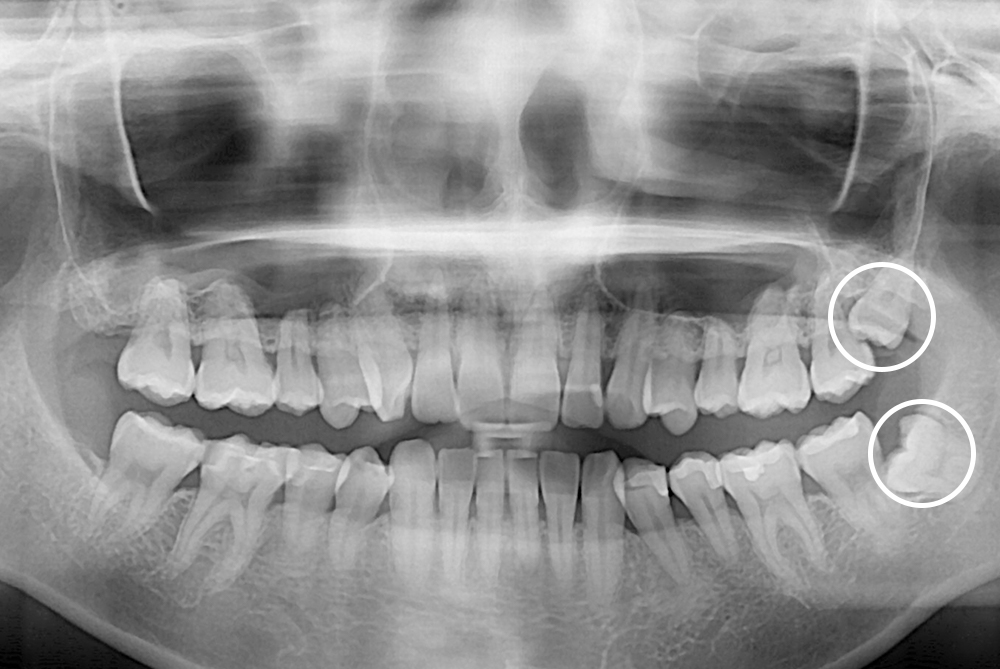

[사랑니] 매복 사랑니 발치

치료전 : 2018-04-14